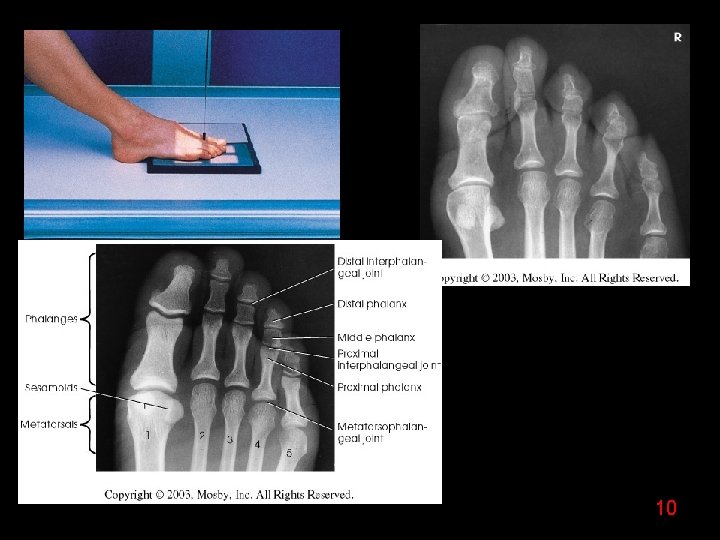

10